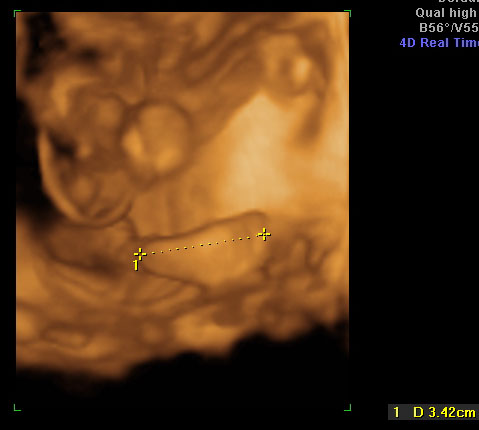

Arckép  A kis boxoló...

A kis boxoló...2007.12.21 20:54

Arckép  A kis boxoló...

A kis boxoló...2007.12.21 21:16